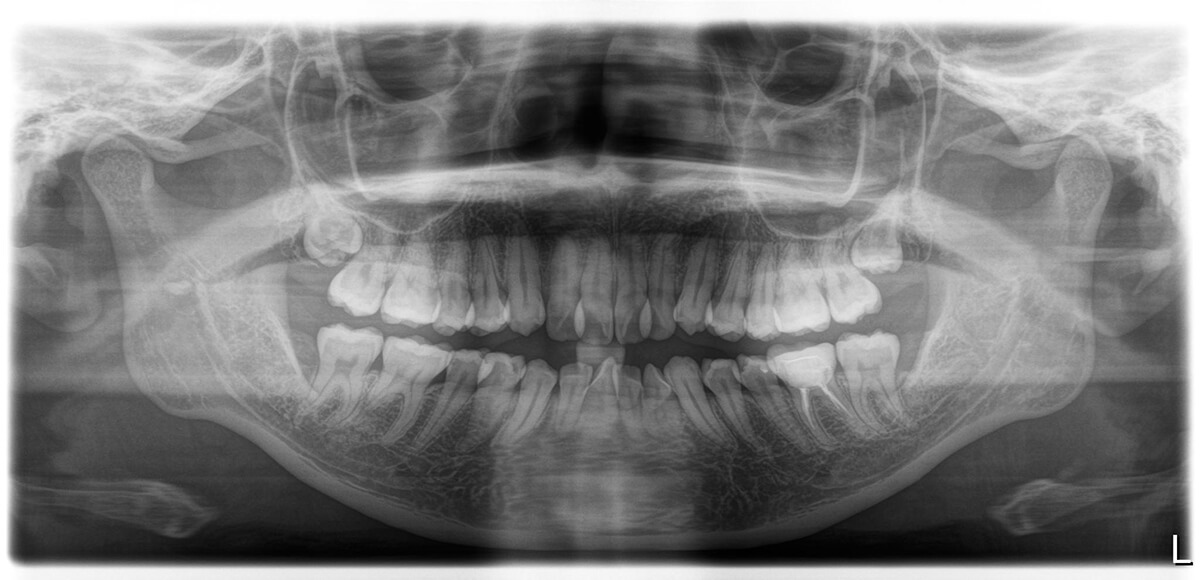

2. パノラマX線撮影

パノラマX線撮影